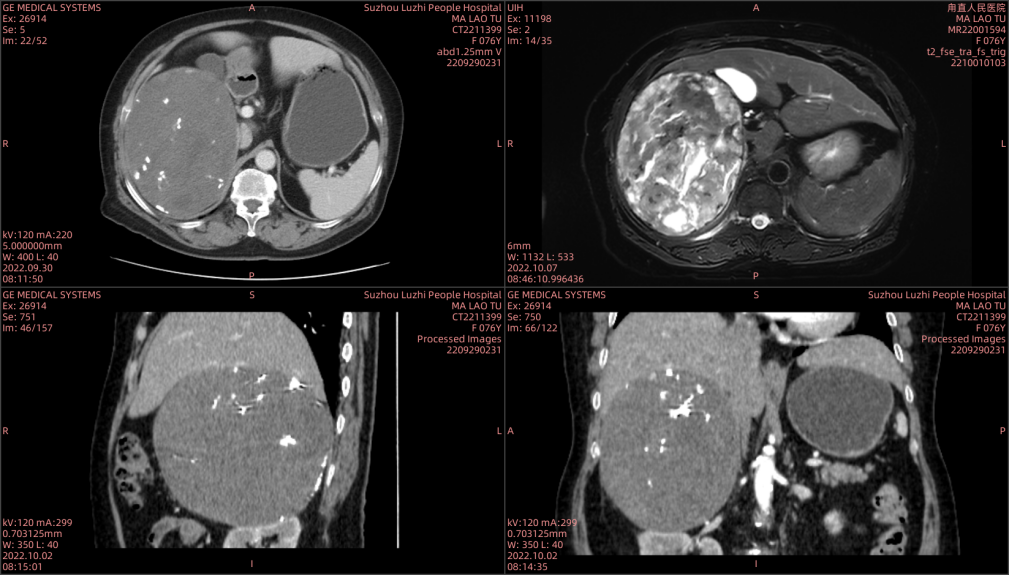

来自苏州吴中区甪直的马老太已过古稀之年,一年前发现自己腹部右侧微微隆起,但当时她觉得没有不舒服,也没当回事,更没有到医院做进一步检查。直到今年10月份,她感觉肚子隐隐作痛,还伴有腹胀、疲倦的感觉,便和家属到当地医院检查,发现果然有问题:右侧腹膜后巨大占位,大小约15cmx12cm。考虑肾上腺皮质腺癌。

CT及MR示:腹膜后巨大占位

然而,想要切除这个像“排球”大的巨大肿瘤并不容易!住院后经检查发现,这个肿瘤来源不明,而且严重挤压右肾及肝脏,与右侧肾上腺关系密切,手术切除肿瘤并保护各重要脏器手术难度巨大。泌尿外科团队立即组织术前全院会诊,邀请普外科、影像科、麻醉科、心内科、重症医学科、内分泌科、肾内科专家进行多学科进行病例讨论。影像科张卫国主任表示,经过详细的检查,初步考虑这是来源于肾上腺的肿瘤,恶性肿瘤的可能性很大,但是从影像检查发现,肿瘤包膜较为完整,除了手术切除之外,其他的治疗方法难以奏效;麻醉科侯永恒主任表示,考虑肾上腺来源的肿瘤有可能是嗜铬细胞瘤,这种肿瘤会影响血压变化,手术切除过程中血压会出现波动,风险极大。